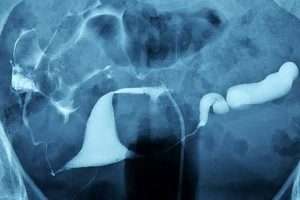

Sol Selektif Salpingografi

Aşağıdaki örneklerde rahim boşluğu ve tüplerin farklı durumlarına ait görüntüler ve kısa açıklamalar yer alır. Rahim sağındaki iri myom kitlesi rahim boşluğu alt kısmının uzamasına ve sola doğru itilmesine sebep olmuş. Rahim boşluğu alt bölümünde yaklaşık 1 cm çaplı polip. Standart HSG’de sol tuba görülmediği için aynı seansda sol selektif salpingografi yapıldı. Her iki tüpün uzak noktadan tıkalı olduğu, sosis gibi şiştiği ve içinde sıvı birikimi bulunduğu görülüyor. Rahim boşluğunun “V” şeklinde olduğu görülüyor. Sağ ve soldaki bölümlerin uzun eksenleri arasında dar açı bulunduğuna dikkat ediniz. Üçgene yakın bir şekilde olması gereken rahmin T harfi şeklinde olduğu görülüyor. Rahim boşluğu tavanı sağında girinti ve bu bölgede rahim duvarı içine doğru uzanan saçaklanmalar görülüyor. Rahim boşluğu sağ-üst köşesinin incelip uzamış olduğuna dikkat edin. Rahim boşluğu içerisinde görülen uzunlamasına gölgelenmeler rahmin iç yüzündeki dalgalı yapıdan kaynaklanmaktadır. Patolojik bir durum değildir. Rahim ağzı kanalının iç deliğe yakın yerinde daha önce geçirilmiş sezaryen operasyonunun izi görülüyor. Bir bölme, tüm rahim boşluğunu rahim ağzı kanalının ortasına kadar ikiye bölüyor. Rahmin vajinaya açılan tek deliği var. Her iki tüp karın boşluğuna açılan ucundaki yapışıklıklar nedeniyle genişlemiş. Görüntü rahmin tam karşısından alınmış. Tüpler normal çapta. Tüplerden karın boşluğuna geçen kontrast madde karın içinde serbestçe dağılmış. Rahmin sağında rahim boşluğuna doğru girinti oluşturan yaklaşık 2 cm çaplı myom. Vajinada saptanan iki girişten 2 kateterle aynı anda kontrast madde verilerek yapılan incelemede muz şeklinde iki ayrı rahim boşluğu görülmektedir. Longitudinal vajinal septası olan olguda iki taraf birden dolduruldu. Tüpler normal çapta ve açık. Sol tüp uzak ucundan tıkalı, şişmiş ve içi sıvı dolu. Her iki taraftaki tüpler orta kesim seviyesinde tıkalı. Tıkalı tüplerin bir beyzbol sopası şeklinde olduğuna dikkat edin. Uterus içinde bazen uzunlamasına muntazam silik bantlar görülebilir. Bunlar uterus iç yüzeyindeki normal dalgalı yapıya aittir. Her iki tüpün uterusa yakın segmenti çevresinde çok sayıda küçük divertikül imajı görülüyor. Sol tüp tıkalı, sağ tüp açık. İnce bir boyunla servikal kanal proksimaline irtibatlı yaklaşık 2 cm çaplı divertikül görülüyor. Uterusun sağa doğru yatık olduğu görülüyor. Bu durum genellikle bir sorun teşkil etmez; bazen yapışıklıklar vb. sebeplerle olabilir. Sol tüp uzak uç bölgesinde tıkalı, şişmiş ve içerisi sıvı dolu. Genellikle öne kıvrık olan uterus bazen arkaya kıvrık olabilir. Bu durum normal bir varyasyondur. Uterin kavite yan duvarlarındaki sineşiler nedeniyle uterin kavite “T” şeklinde görülüyor. Uterin kavite solunda düzensiz kitlesel dolum defekti ve kavite alt bölümde genişleme. Biyopsi sonucu: Endometrium kanseri. Uterin kavite üst segmentte sağda ve solda birer adet endometrial polip görülüyor. Uterin kavite alt kesimde görülen etek şeklindeki genişleme geçirilmiş sezaryen ameliyatı kesisinden kalan bir sekeldir. Birbirinden ayrık, muz şeklinde 2 uterin kavite ve onların bağlı oldukları tek servikal kanal görülüyor. Tüpler açık ve normal. Sağ tüp normal. Şişmiş olan sol tüpün uç kısmı künt sonlanıyor. Az miktarda kontrast sızıntı şeklinde karın boşluğuna geçiyor. Normalde üçgene benzeyen rahim boşluğunun tavanının düz değil konkav olduğu görülüyor. Sağ ve sol tüp uzak ucundan tıkalı. Tüpler sosis gibi şişmiş ve içleri sıvı dolu. Özel kateterle doğrudan sol tüpün içine verilen kontrast madde ile sol tüp açıldı. Kateterin pozisyonu ve açılma görülüyor. Öne eğik uterus tam karşıdan görüntülenmiş. Tüplerin içindeki sağlıklı mukoza kıvrımları paralel çizgiler şeklinde net görülebiliyor.HSG / Selektif Salpingografi Örnekleri